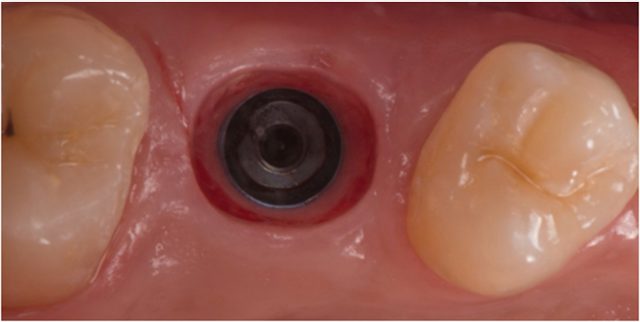

Botones de Sanado

Son aditamentos para los implantes dentales.

Realizando la cirugía de segunda fase. Se colocan los botones de sanado. Cuando el implante dental ha finalizado el proceso de osteointegracion. Se sutura.

Se espera a que la encia sane alrededor del healing cap (Botones de Sanado)